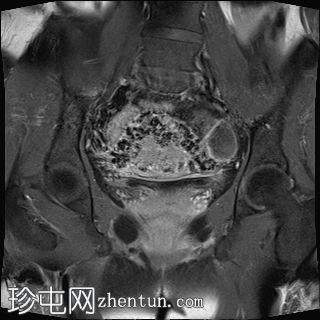

冠状位

T2加权像

子宫增大且体积较大。扩张的血管主要位于子宫后壁(符合子宫动静脉畸形)。

子宫内膜肌层交界处也存在异常。

子宫内膜腔显影清晰,外观正常。